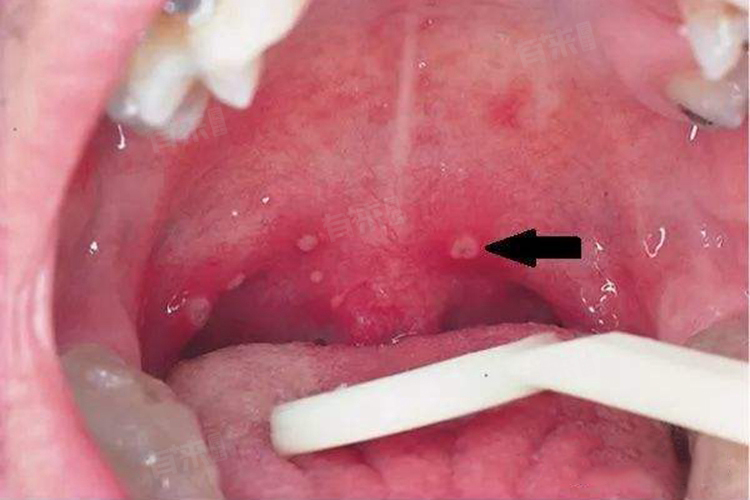

喉咙可能会长溃疡。喉咙部位的溃疡病灶常常会引起明显的疼痛感,尤其是在做吞咽动作时会引起更为严重的疼痛感。喉咙里出现溃疡的原因可能包括: